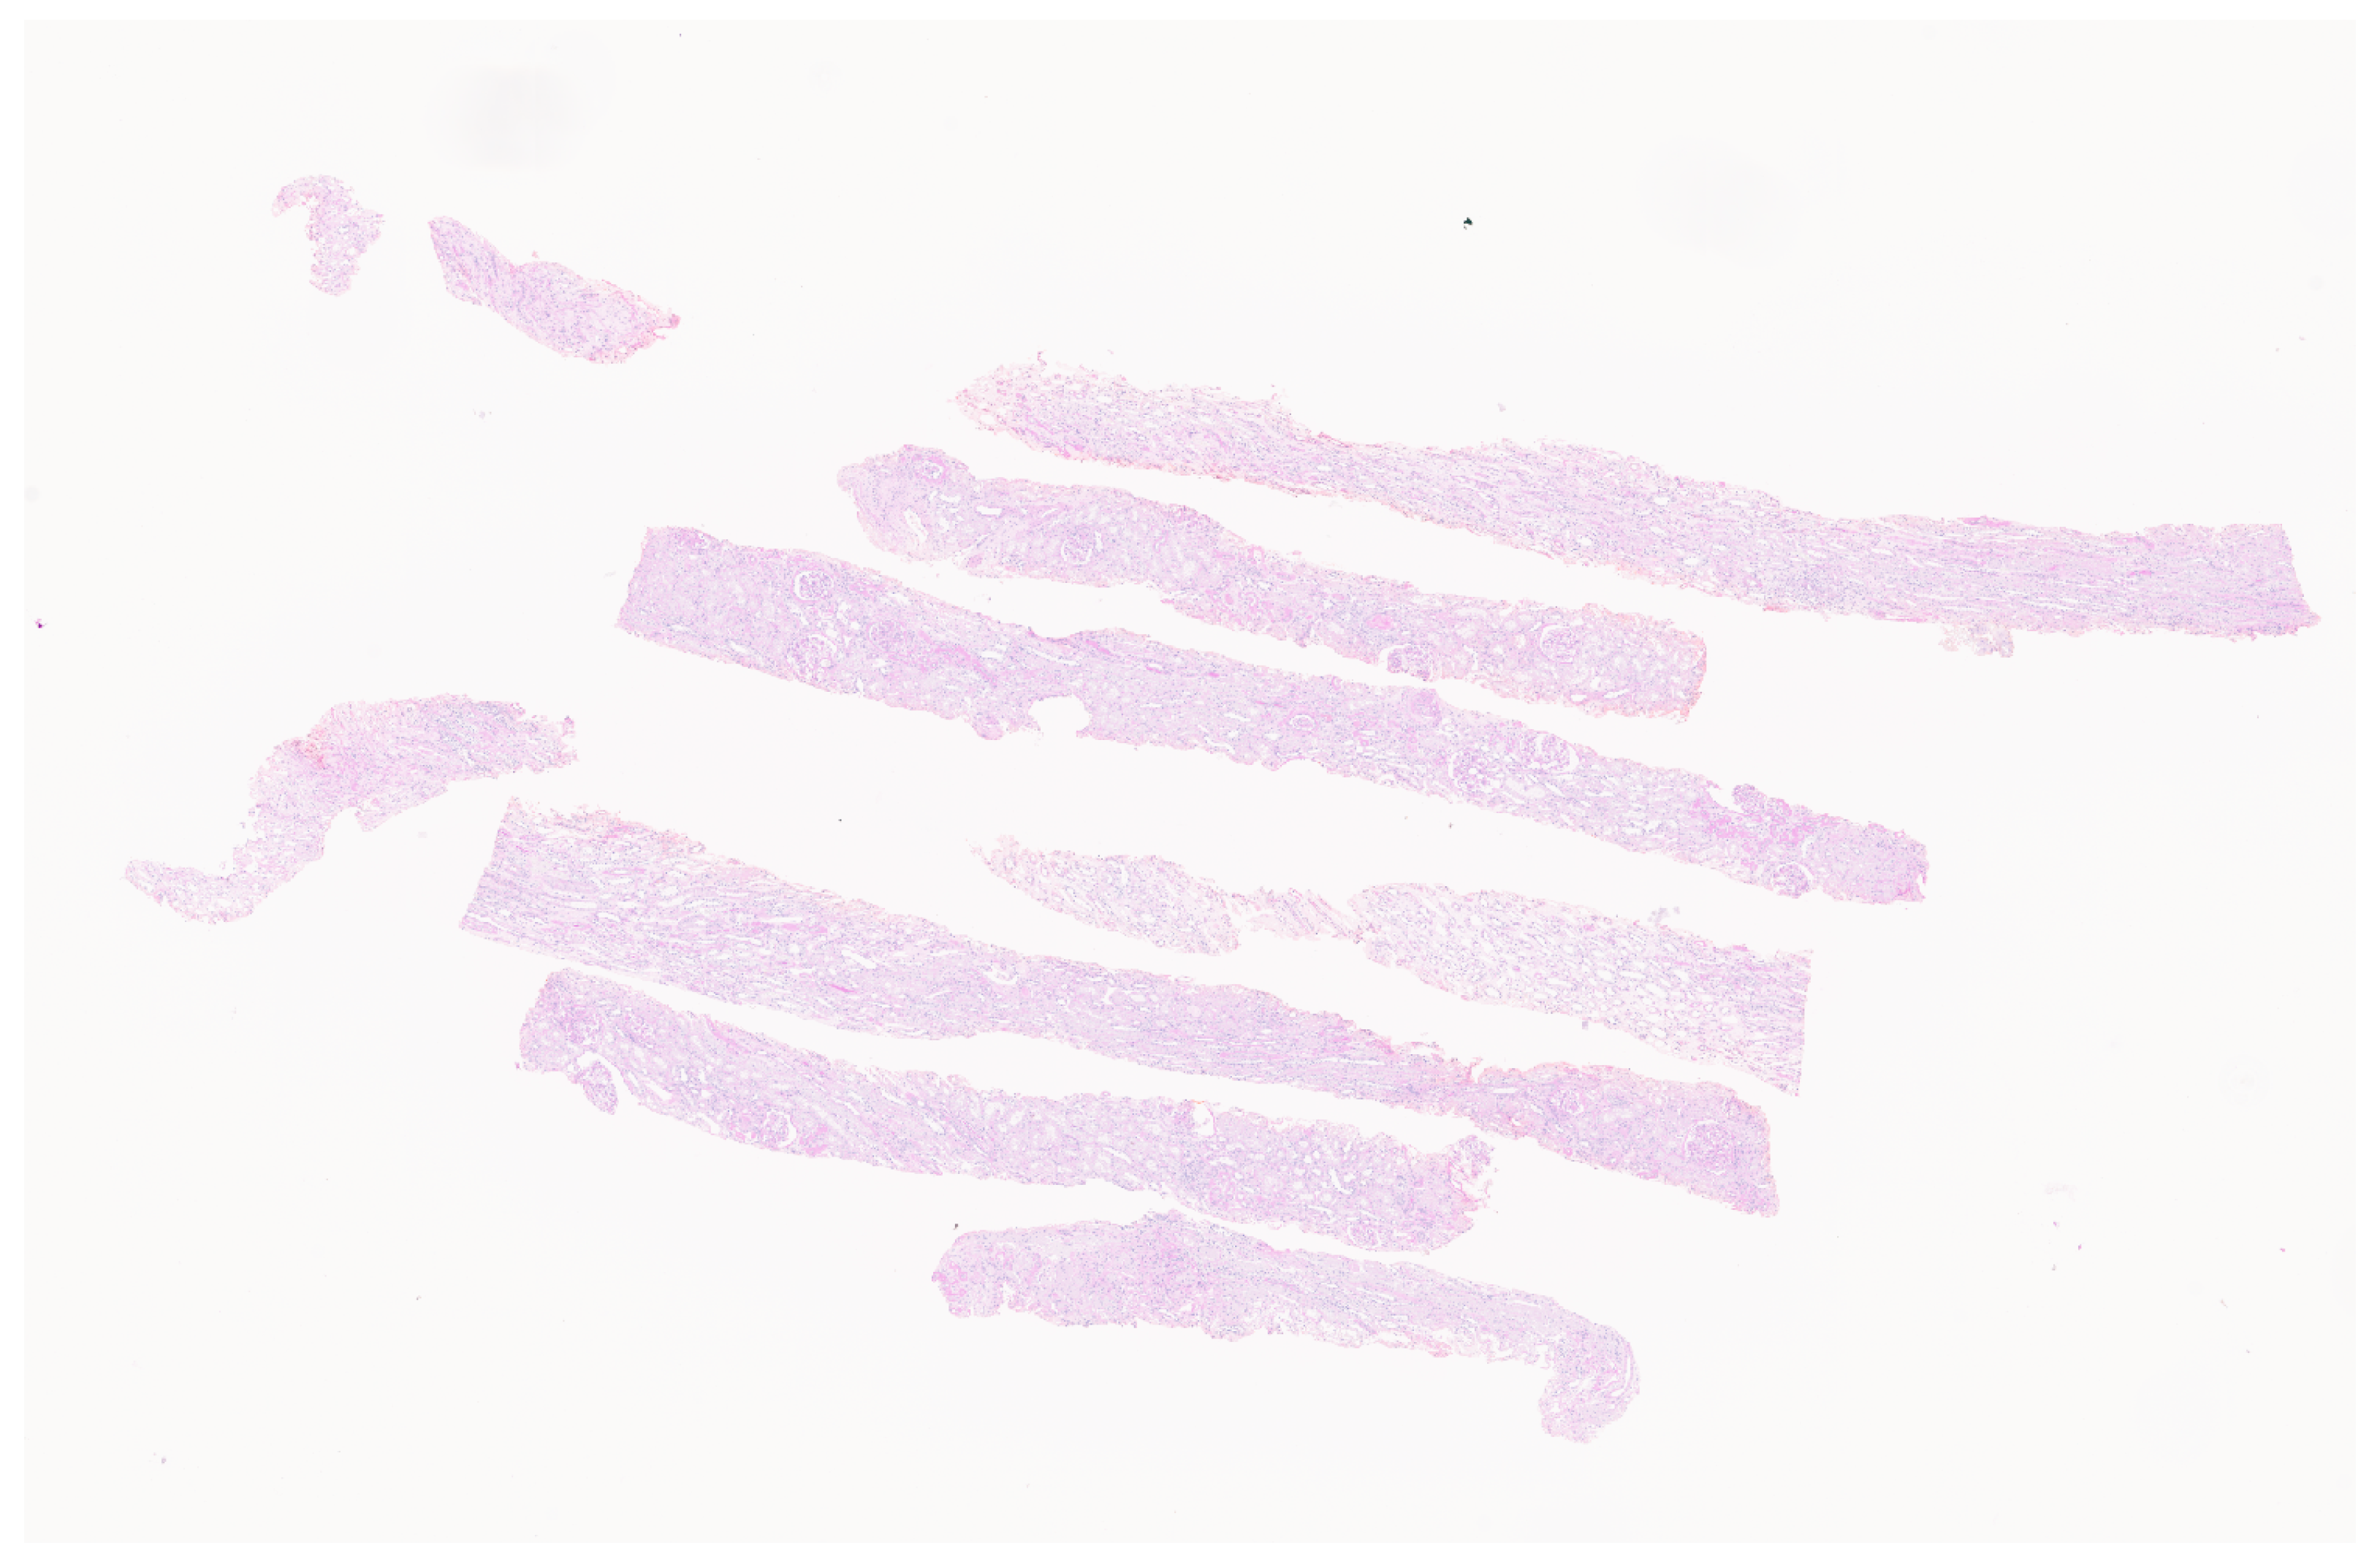

The mouse glomerulus image dataset comprised high-resolution WSIs of pathological kidney specimens stained with hematoxylin-eosin dyes [24]. The specimens were obtained from animal experiments. The digitization of these images was performed with the virtual sliding Leica Aperio Scan Scope, ID number SS1061, Leica Corp., Wetzlar, Germany [24]. The images were digitized at a maximum magnification of 20× and a spatial resolution of 0.5 microns per pixel (mpp) [24]. The original pathological images were processed and selected to give 5000 image patches with glomerulus at a size of 256 × 256. Figure 1 shows the original WSI of a mouse kidney affected by 1% cholesterol and 0.25% sodium cholate.

To avoid the morphology of the glomerulus of mouse under different regimens affecting the results, equal-sized sets of images for two different drug regimens affecting inputs were selected. The dataset formed by images affected by 1% cholesterol and 0.25% sodium cholate was called mouse dataset A. The dataset formed by images affected by nitrofluorene was called mouse dataset B.

Figure 1. An original WSI of a mouse kidney with an actual size of 75,695 × 22,500.